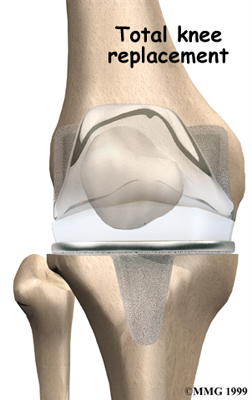

Artificial Knee Replacement

An artificial knee replacement is the ultimate solution for advanced knee OA.

Surgeons prefer not to put a new knee joint in patients younger than 60. This is because younger patients are generally more active and might put too much stress on the joint, causing it to loosen or even crack. A revision surgery to replace a damaged prosthesis is harder to do, has more possible complications, and is usually less successful than a first-time joint replacement surgery.

Related Document: FYZICAL San Francisco's Guide to Artificial Joint Replacement of the Knee